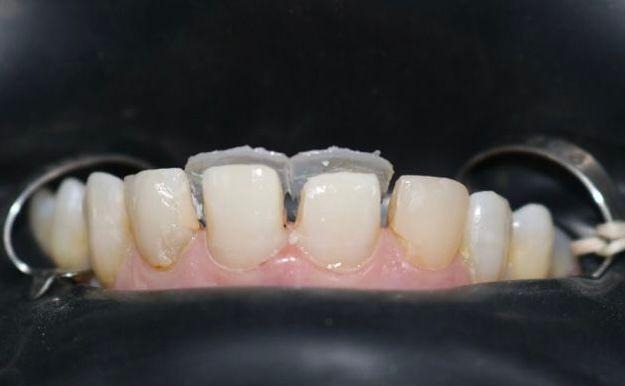

O procedimento clínico teve início com a remoção cuidadosa das facetas antigas com broca multilaminada em alta rotação (figura 6). Em seguida foi realizada a anestesia com o anestésico mepivacaína 2% com epinefrina 1:100.000 (DFL). Os dentes foram devidamente isolados com campo operatório absoluto, após o isolamento foi feita a lavagem da superfície com clorexidina 2%, seguido de ataque ácido fosfórico 37% por um período 15 segundos (MAQUIRA) e lavagem pelo mesmo período de tempo. Aplicação do sistema adesivo universal (FGM), fotopolimerizado por 20 segundos. Em seguida a confecção das conchas palatinas utilizando a resina trans (FORMA), (figura 7).

Figura 6: Remoção das facetas insatisfatórias

Figura 7: Isolamento e conchas palatinas nos incisivos.